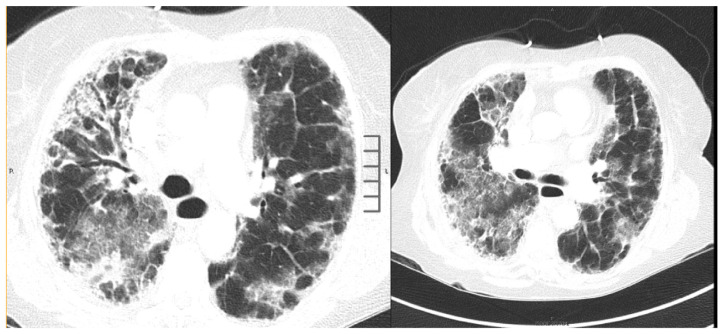

Systemic sclerosis sine (latin: without) scleroderma (ssSSc), also called visceral scleroderma, is characterized by internal organ involvement and abnormal serologic abnormalities in the complete or partial absence of cutaneous manifestations of systemic sclerosis.1,2 Pulmonary involvement in scleroderma consists of interstitial lung disease and pulmonary hypertension. Usual interstitial pneumonia (45.4%), followed by nonspecific interstitial pneumonia (36.4%) represents the predominant interstitial lung disease in scleroderma.3 Rarely, organizing pneumonia has been described with scleroderma and seldom with systemic sclerosis sine scleroderma in literature.